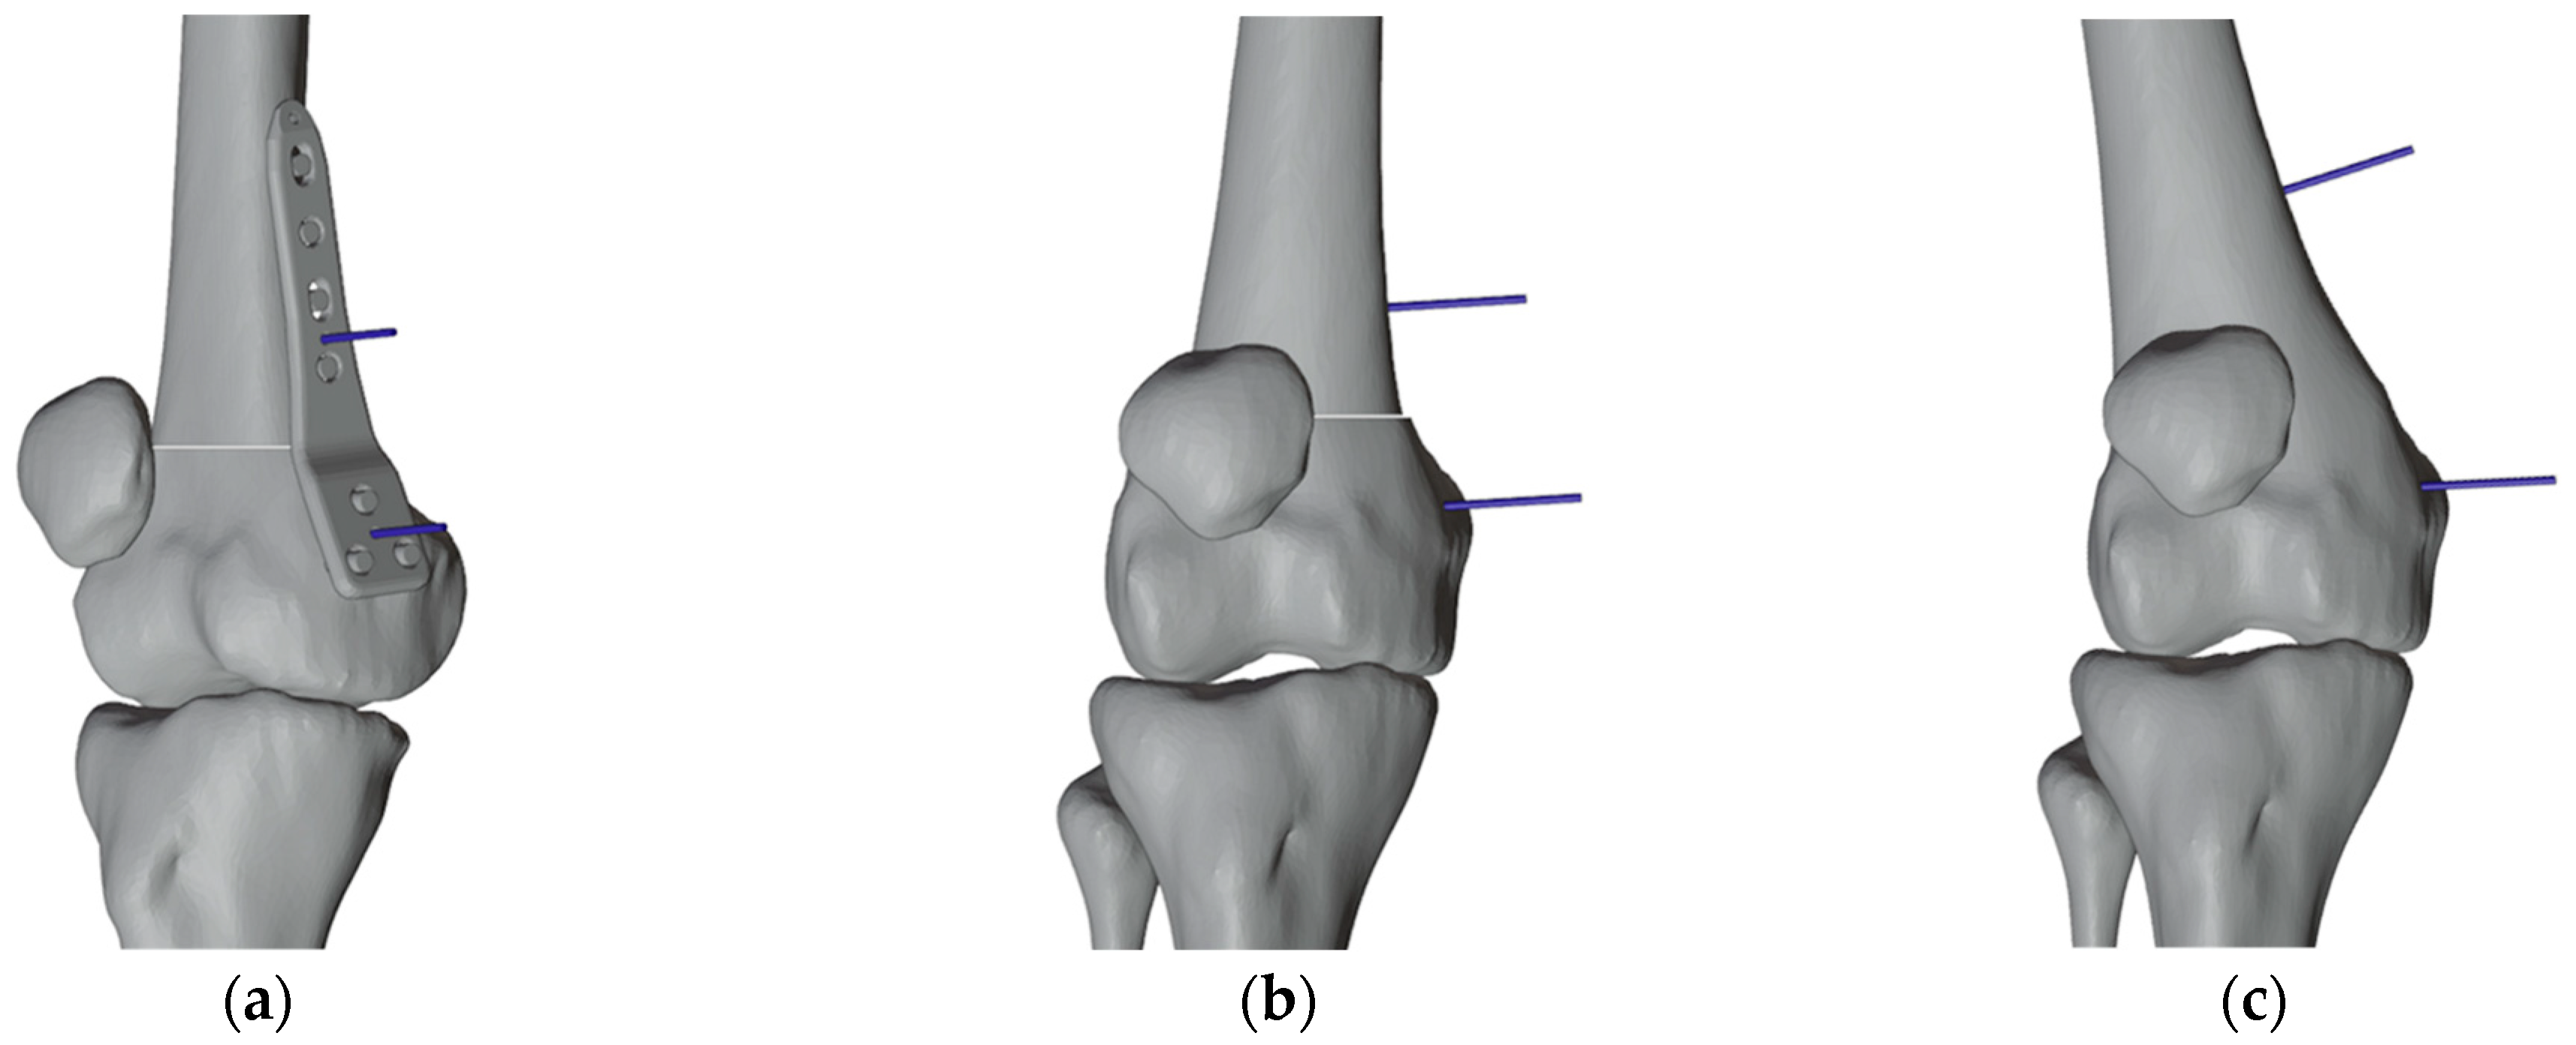

2.3. Surgical Simulation and Planning

2.4.1. PSIs Design for the Right Femur

2.4.2. PSI Design for the Left Femur